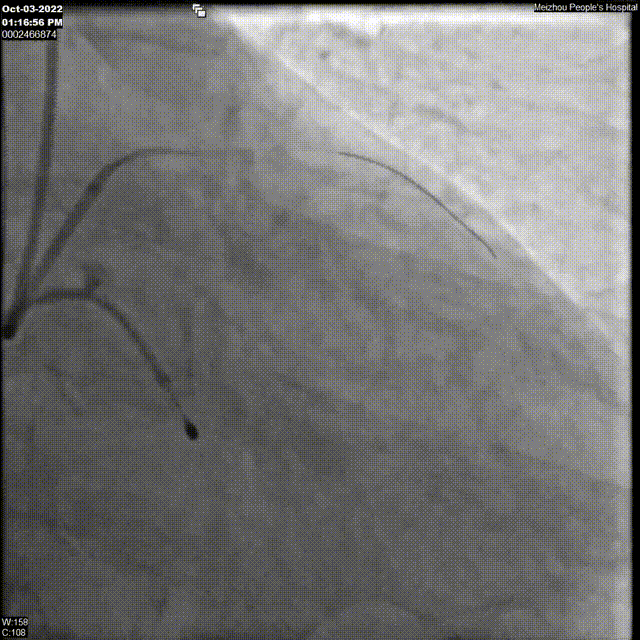

18F球囊预扩张影像

瓣膜植入影像